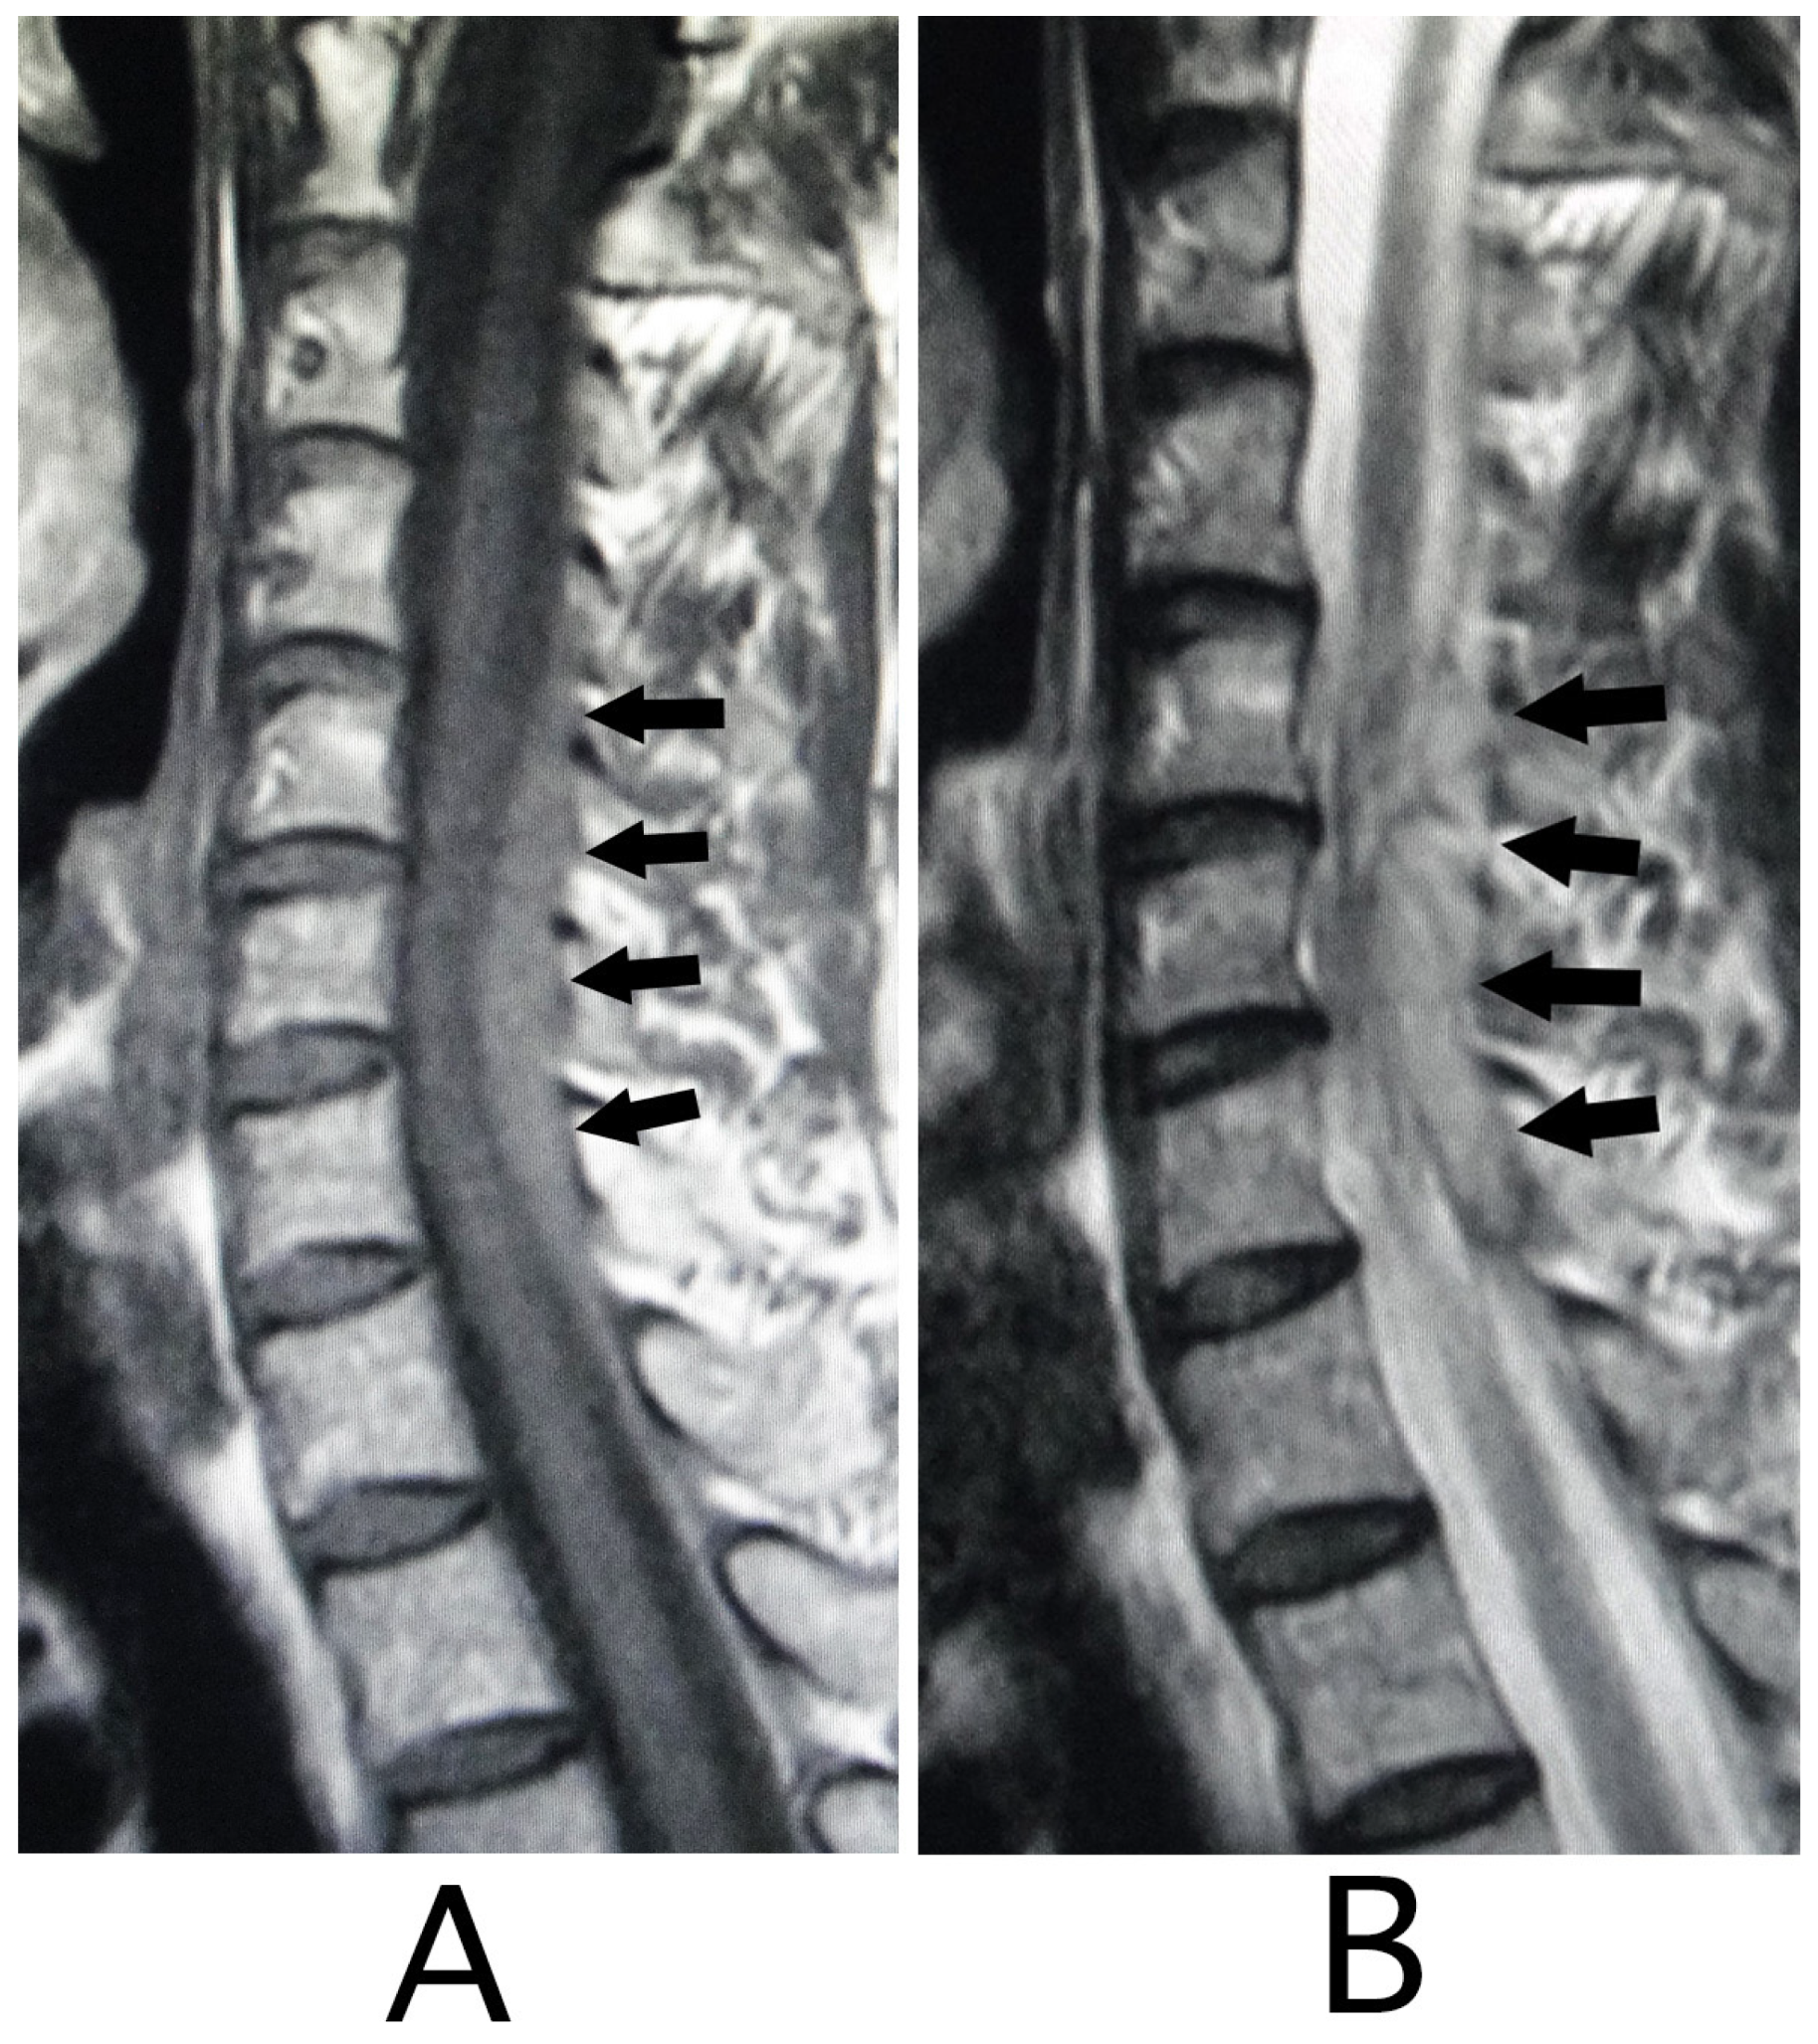

The lesion in the intracranial region or the cervical spinal cord was suspected. Computed tomography (CT) images of the head and X-ray of the cervical bone were normal; however, sagittal CT images of the cervical bone showed a slightly abnormal high-density area (HDA) behind the spinal cord at the level between C4 and C7 (Figure 3A). This abnormal HDA was located in the posterior part on the right side in axial CT images (Figure 3B). MRI analysis was performed because the presence of a hemorrhagic lesion was suspected, based on the CT findings of the cervical bone. Sagittal T1-weighted MRI showed an iso-intensity mass in the epidural space behind the spinal cord at the level from C4 to C7 (Figure 4A). The lesion was noted as a heterogeneous high-intensity mass in sagittal T1-weighted images (Figure 4B). Axial T1-weighted MRI showed an iso-intensity mass in the posterior part on the right side in the epidural space and mild compression of the spinal cord (Figure 5A). The lesion was noted as a heterogeneous high-intensity mass in axial T2-weighted images (Figure 5B).

Figure 5. Axial MRI. An iso-intensity mass was identified in the diagonally posterior part on the right side (white arrows) (T1-weighted image; (A)). The lesion was visualized as a heterogeneous high- intensity mass (black arrows) (T2-weighted image; (B)). Mild compression of the spinal cord by the lesion was shown (A,B). (Rt = right).